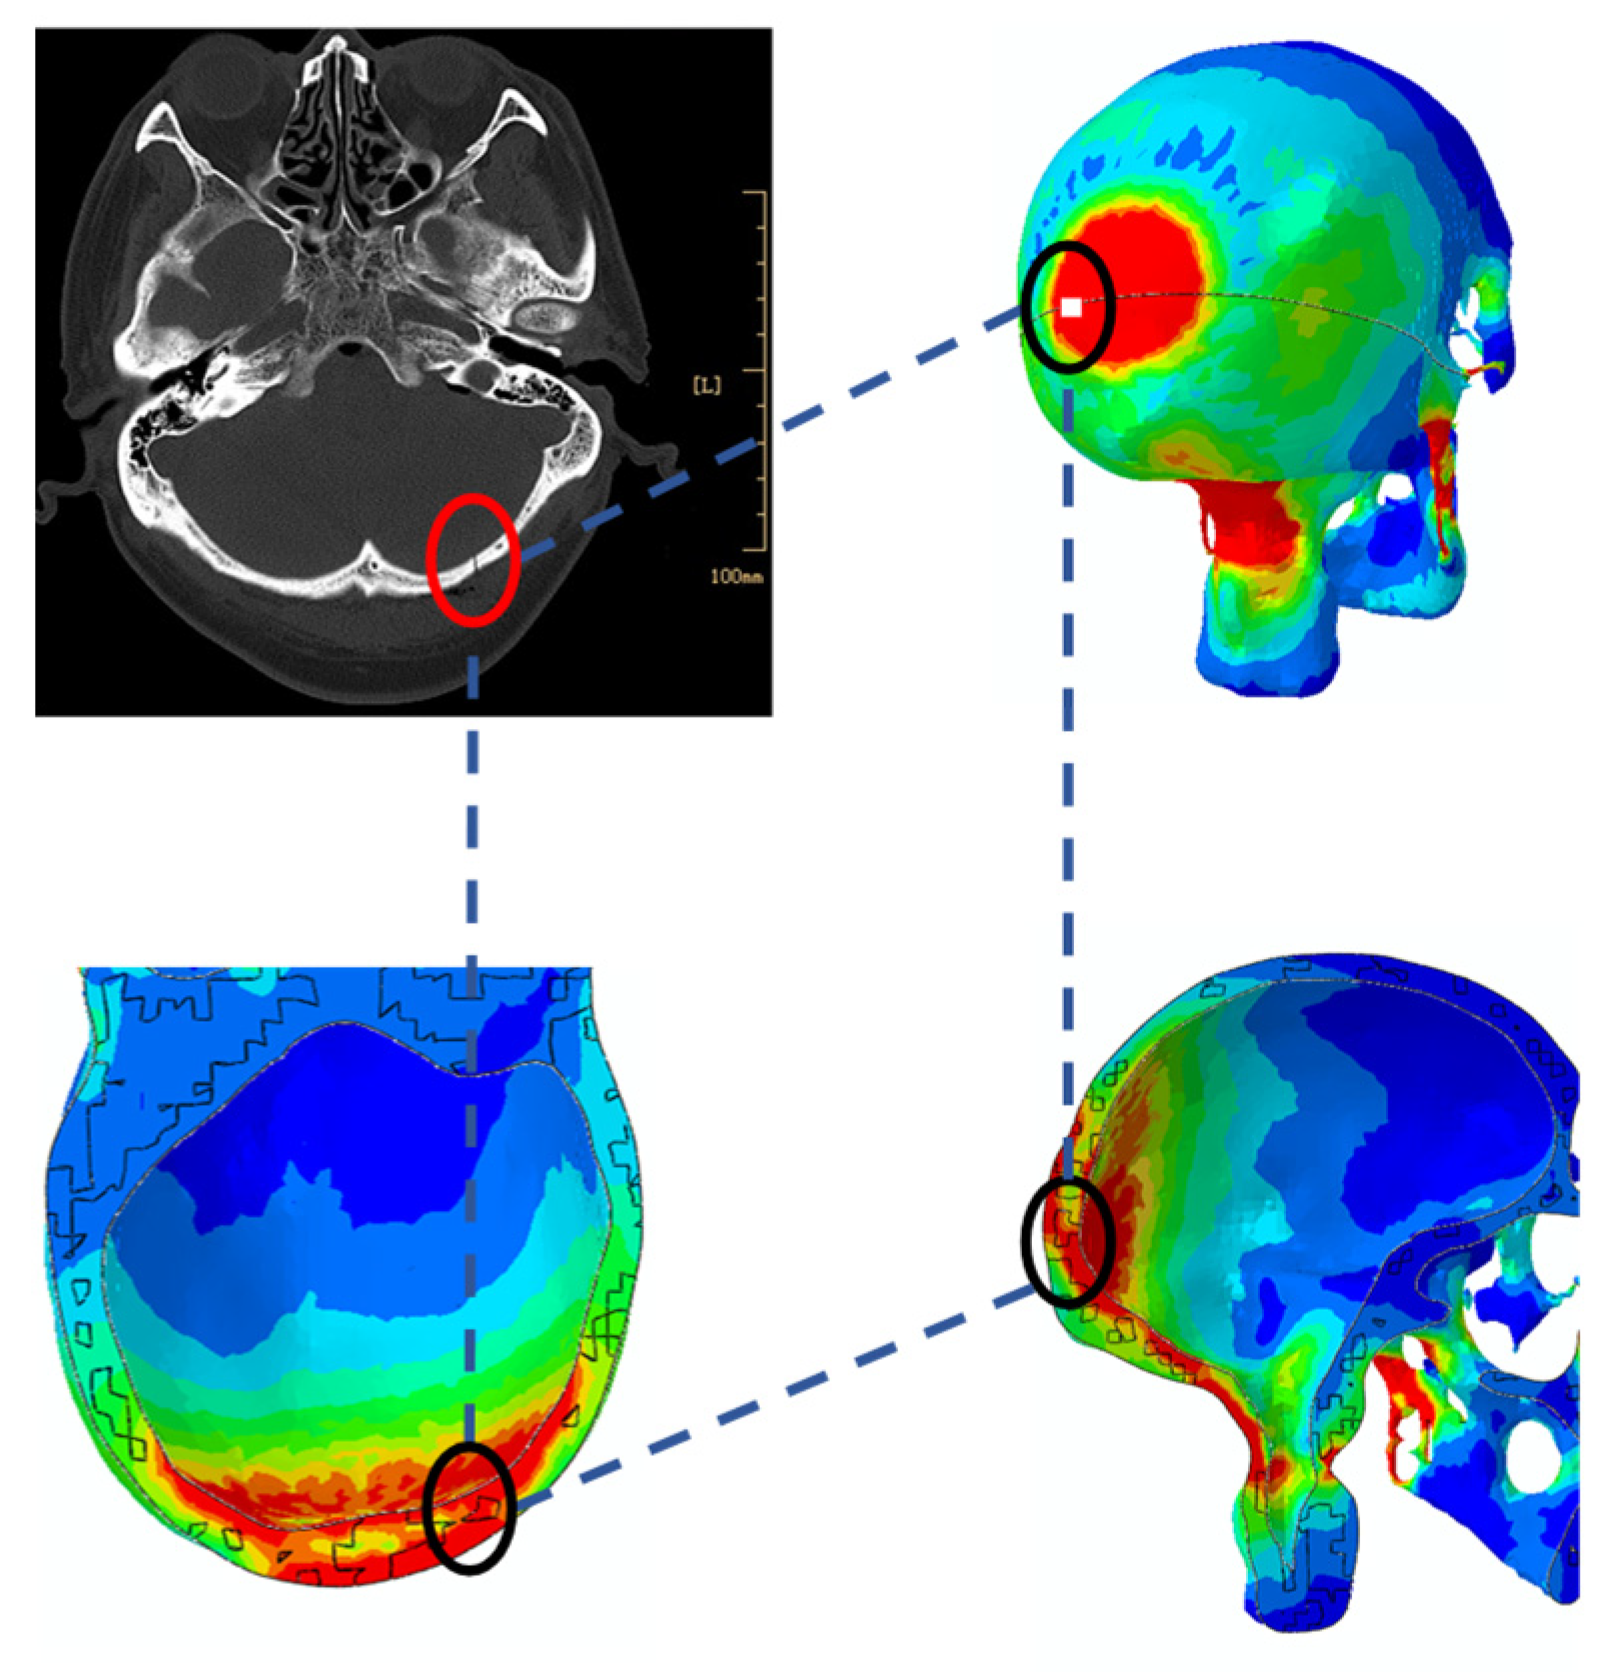

3.1. Skull Injury under Different Impact Conditions

3.2. Effects of Impact Angle on Peak Stress Value of the Skull